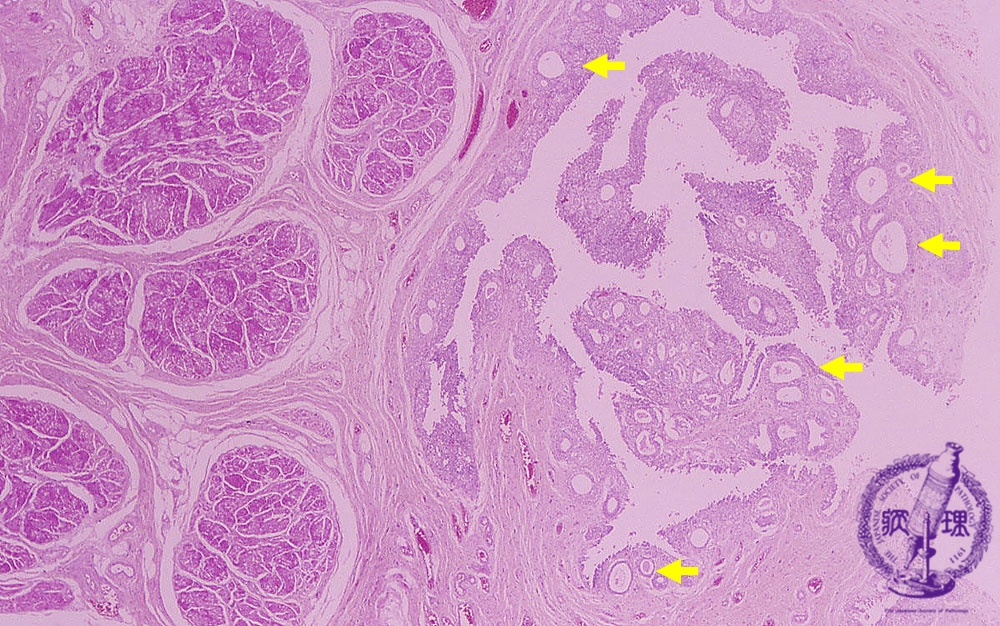

Microscopic findings (HE, high power view): Cystitis cystica. The von Brunn’s nests are dilated to form cystic lesions (yellow arrows).